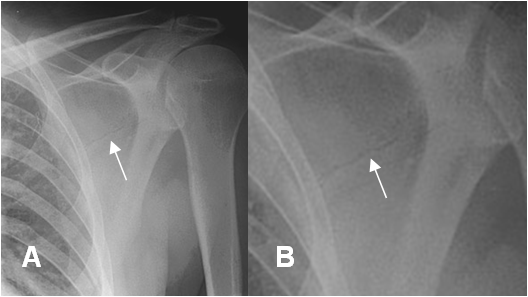

Fig 57. Fractura de escápula.

A: Rx AP de hombro y B: Magnificación. Fractura transversa, en el tercio medio de la escápula.